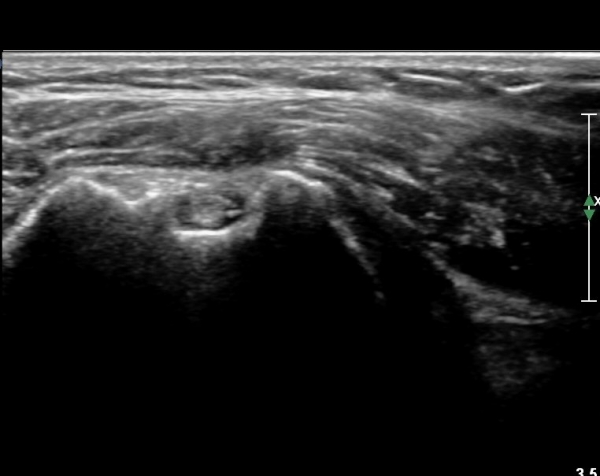

ȸÀü±Ù°³°£°Ý(rotator cuff interval) Ⱦ´Ü¸é°Ë»ç¿¡¼­ ÀÌµÎ¹Ú±Ù°Ç ¿ÜÃø¿¡ ±Ø»ó°ÇÀÌ °üÂûµÇÁö ¾Ê°í

´ë°áÀý Ç¥ÃþÀÇ »À°¡ ¿ïÅüºÒÅüÇÏ°Ô º¯ÇÏ¿´´Ù(±×¸² 1, 2)

ÀÌ´Â ½ÉÇÑ Ãæµ¹ÁõÈıºÀÇ °á°úÀ̰í ȸÀü±Ù°³ ÆÄ¿­À» °­·ÂÈ÷ ¾Ï½ÃÇÏ´Â ¼Ò°ßÀÌ´Ù.